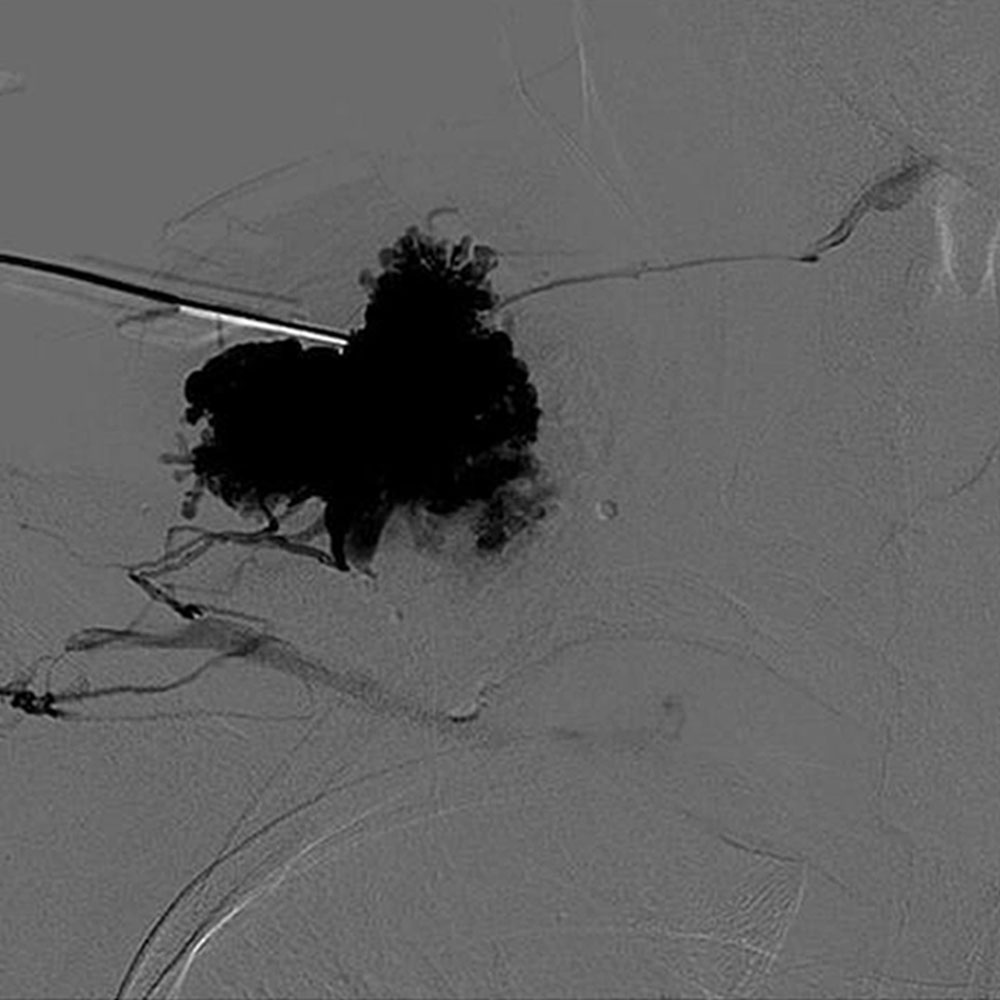

Die aszendierende Phlebographie dient zur Klärung von Aplasien und Dysplasien des tiefen Venensystems, wenn Duplex-Sonographie und MRT keine sichere Beurteilung ermöglichen. Die Indikation ist somit auf sehr spezielle Fragestellungen begrenzt. Die wesentliche Bedeutung der phlebographischen Darstellung durch Direktpunktion liegt in der Durchführung einer Sklerosierung der venösen Malformation.